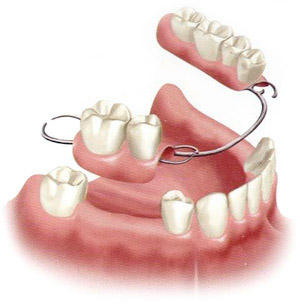

Hàm Tháo Lắp

Gồm có nền hàm để giúp hàm giả bám vào niêm mạc miệng và các răng bên cạnh. Các răng giả được cấy trên nền hàm đó. Nền hàm có thể làm từ